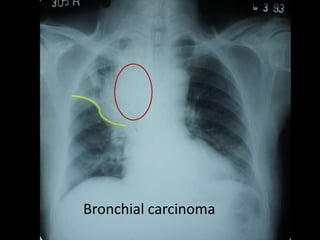

Bronchial carcinoma

air crescent sign Fungalball - aspergilloma